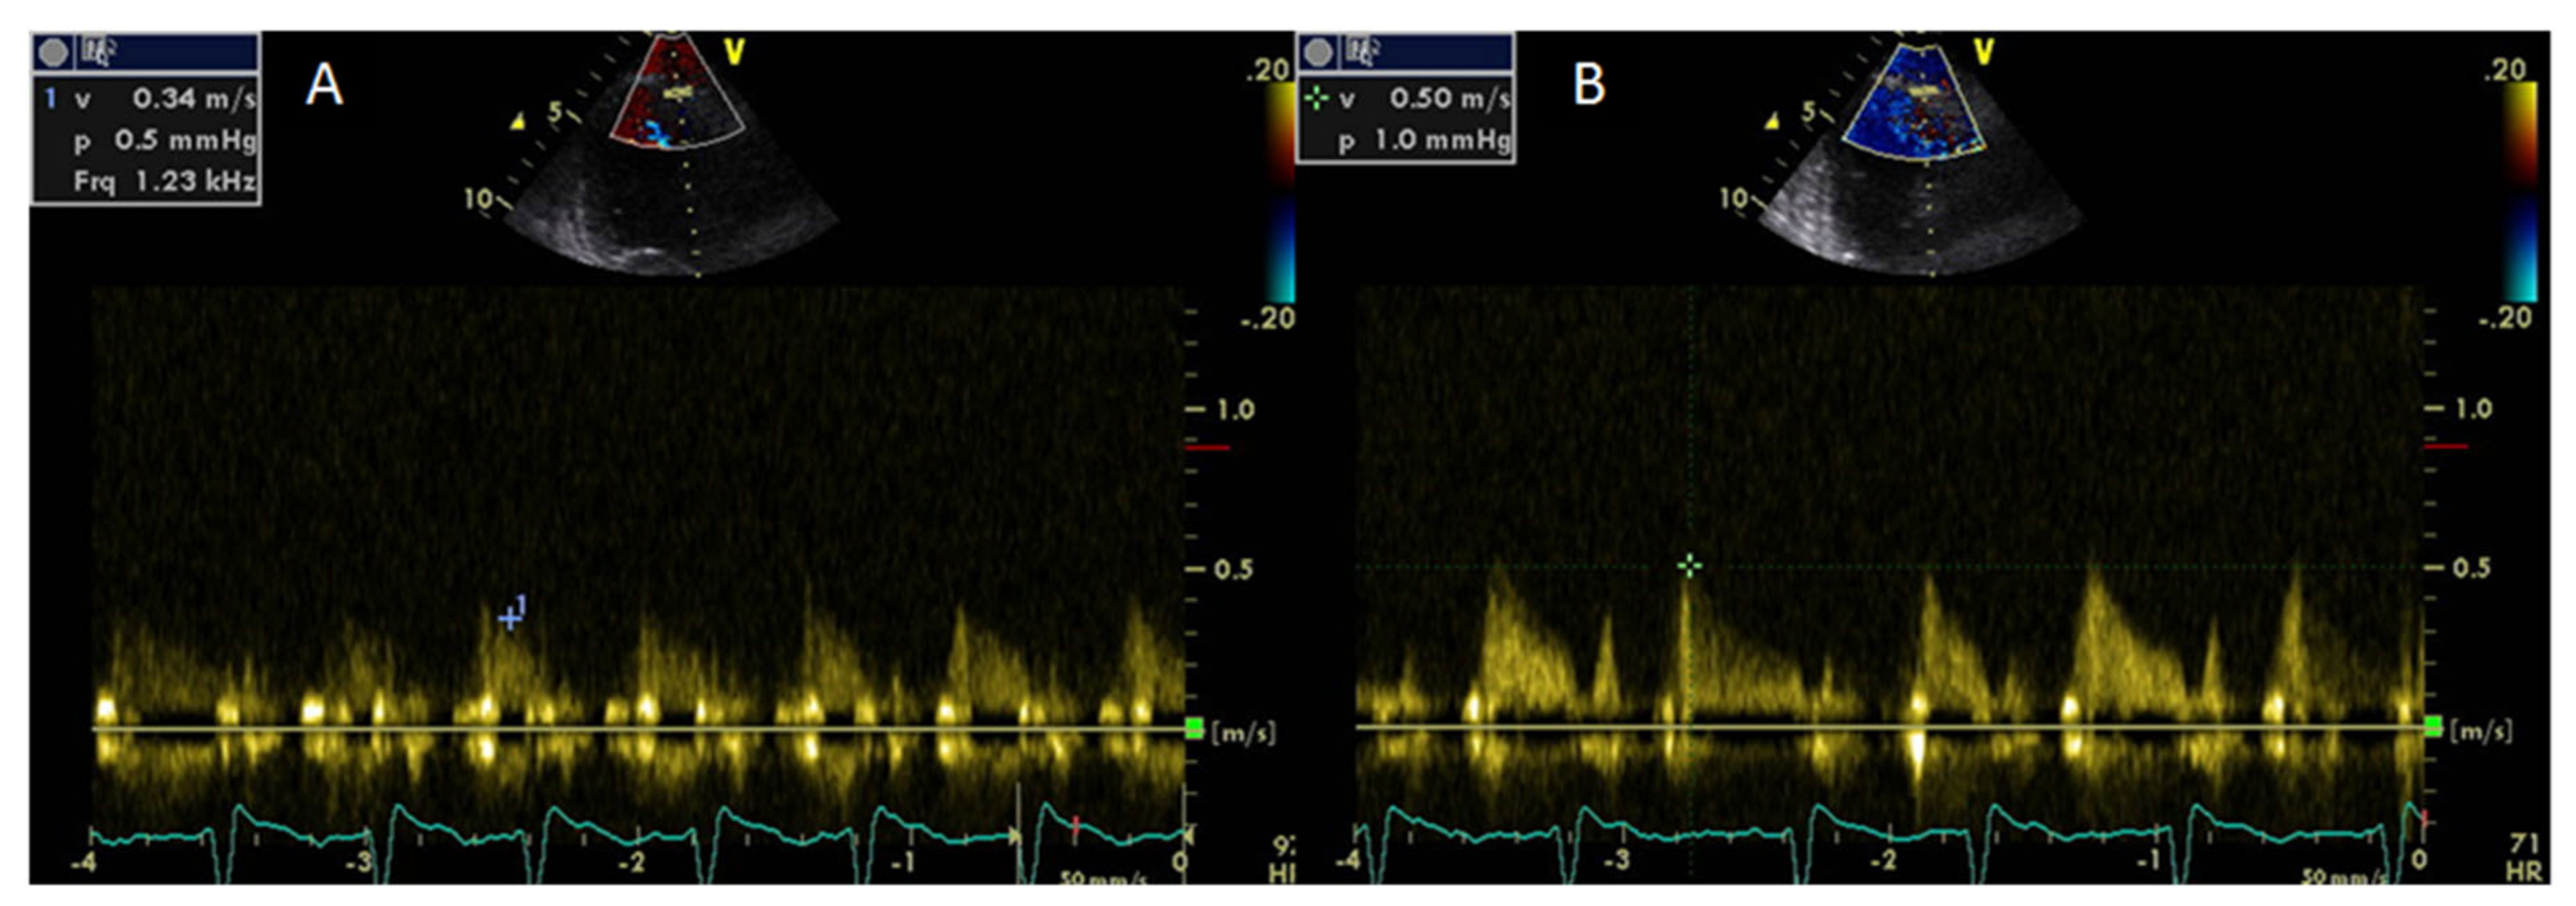

- Meimoun, P.; Tribouilloy, C. Non-invasive assessment of coronary flow and coronary flow reserve by transthoracic Doppler echocardiography: A magic tool for the real world. Eur. J. Echocardiogr. 2008, 9, 449–457. [Google Scholar] [CrossRef]

- Hozumi, T.; Yoshida, K.; Akasaka, T.; Asami, Y.; Ogata, Y.; Takagi, T.; Kaji, S.; Kawamoto, T.; Ueda, U.; Morioka, S. Noninvasive assessment of coronary flow velocity and coronary flow velocity reserve in the left anterior descending coronary artery by Doppler echocardiography: Comparison with invasive technique. J. Am. Coll. Cardiol. 1998, 32, 1251–1259. [Google Scholar] [CrossRef]

- Erre, G.L.; Buscetta, G.; Paliogiannis, P.; Mangoni, A.A.; Carru, C.; Passiu, G.; Zinellu, A. Coronary flow reserve in systemic rheumatic diseases: A systematic review and meta-analysis. Rheumatol. Int. 2018, 38, 1179–1190. [Google Scholar] [CrossRef]

- Turiel, M.; Atzeni, F.; Tomasoni, L.; de Portu, S.; Delfino, L.; Bodini, B.D. Noninvasive assessment of coronary flow reserve and ADMA levels: A case-control study of early rheumatoid arthritis patients. Rheumatology 2009, 48, 834–839. [Google Scholar] [CrossRef] [PubMed]

| Impaired coronary flow reserve | Coronary Flow Reserve >2 |